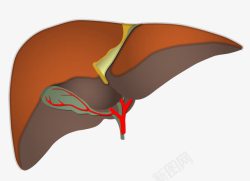

肝脏器官图标

人体肝脏

肝脏器官图标